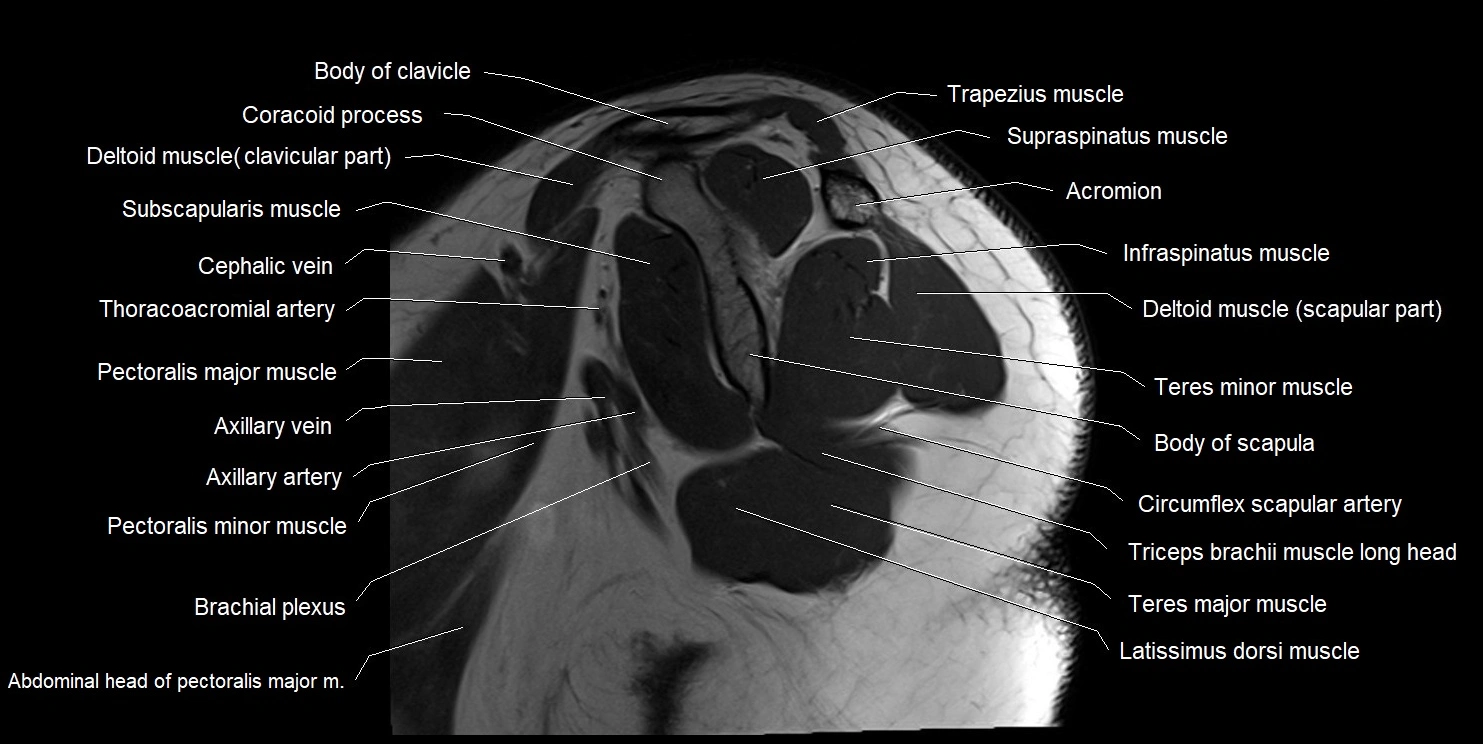

MRI images

image